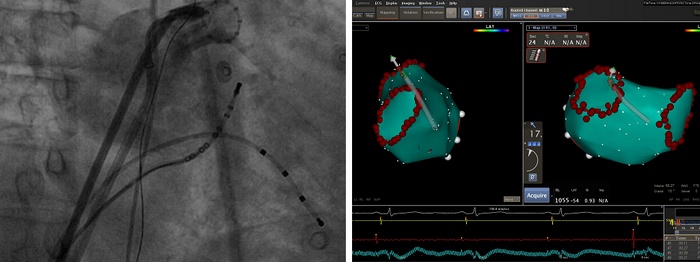

6月19日和21日,我院心内科先后顺利完成两例房颤射频消融术,哈特瑞姆医生集团提供技术支持,术后患者均恢复正常心律,无任何不适。短时间内两例手术的成功开展标志着我院心内科在心律失常介入治疗领域取得重大突破,房颤射频消融治疗已成为心内科的常规治疗手段。

射频消融手术是根治房颤的介入治疗手术。该手术通过穿刺静脉血管,将2-3mm粗的电极导管送入左心房、肺静脉内进行三维建模,对房颤病灶进行精细标测,利用射频消融能量损毁心房、肺静脉口部的异常电活动组织,以达到根治房颤的目的。